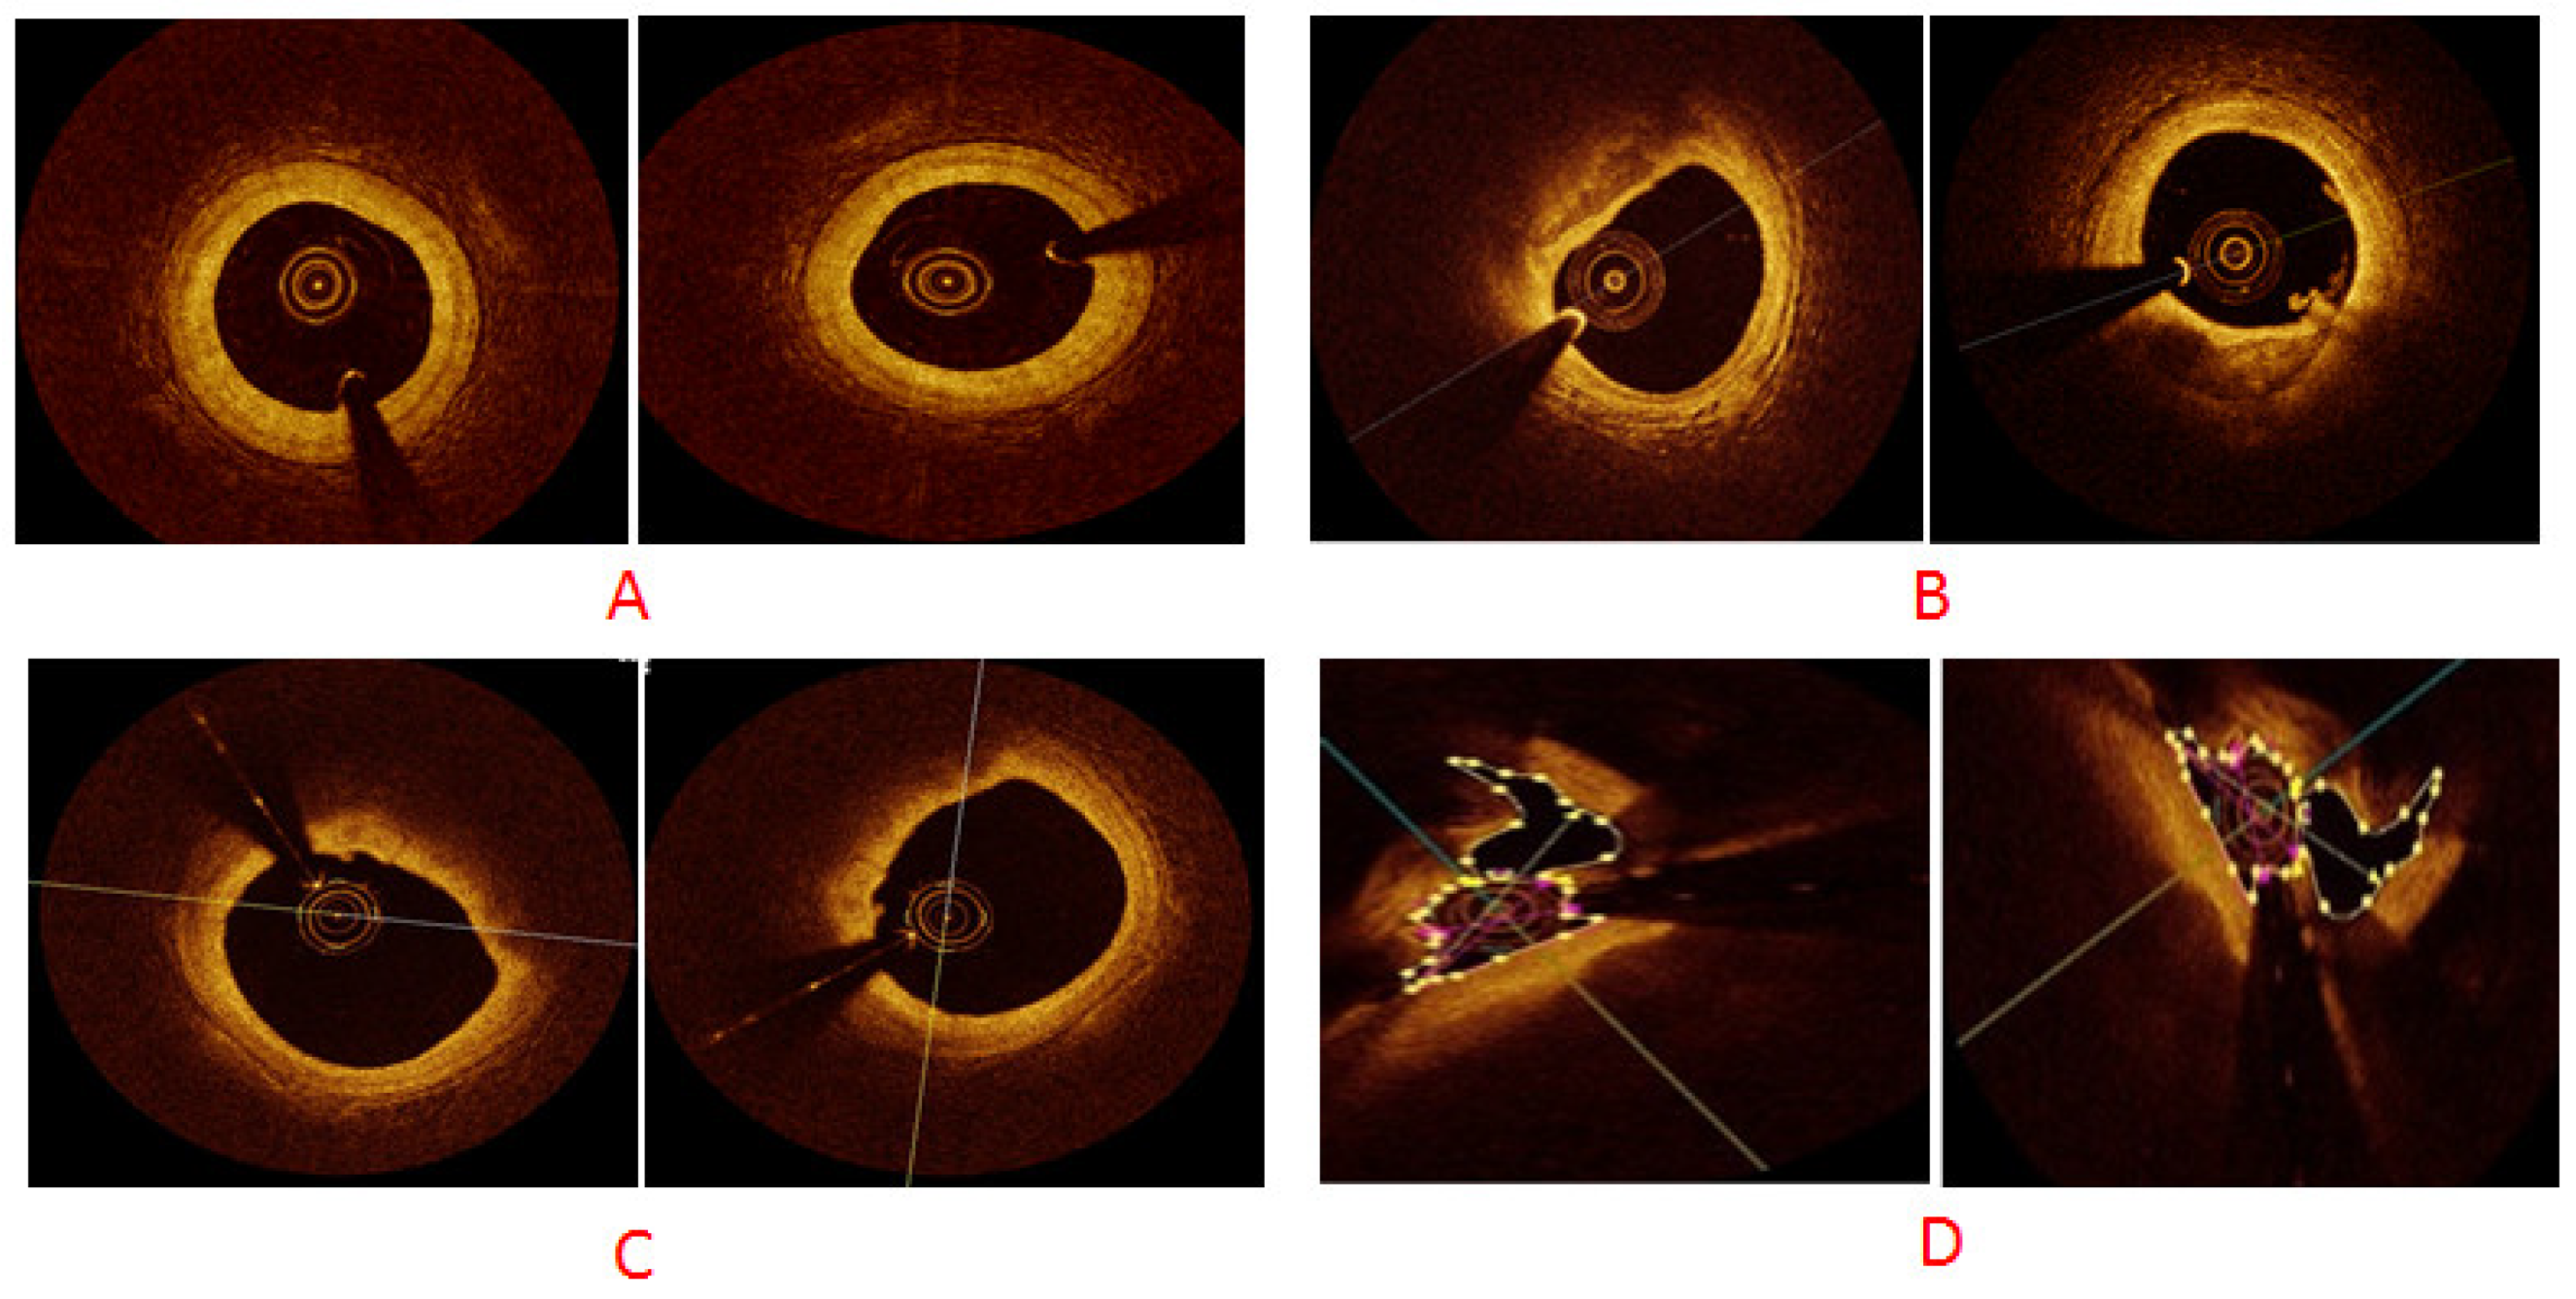

We performed simulations on the newly created OCT dataset, which contained 146 original images belonging to four classes that were then augmented using cGAN with multiplication factors of 5×, 10×, 50× and 100×. The × indicates images acquired via OCT and factor indicates images generated using augmentation. We used 70:30 factors for training and testing purposes. We used TensorFlow, an open-source framework (v2.10.0), to build the model and to implement it. We used CUDA to accelerate training a batch size of 64. For model training, a momentum of 0.9 was used with an initial learning rate of Lr = 10−4. This initial value of momentum helped accelerate training and converge the optimization cycle at the end of training. The learning drop factor was 0.1 with a learning drop rate period of five. The Adam optimizer was used to update network weights. Our model distinguished the coronary arterial plaques in a time-competitive fashion. The results were considered using the testing dataset, whereas assorted hyper-parameters were performed using the validation set. Figure 6 exhibits GANs-generated sample images of our four classes; namely, normal, calcified, lipid and mixed atrial plaques.

Figure 6. cGAN-generated synthetic sample images for different classes: (A) normal plaque, (B) calcium plaque, (C) lipid plaque and (D) mixed plaque.